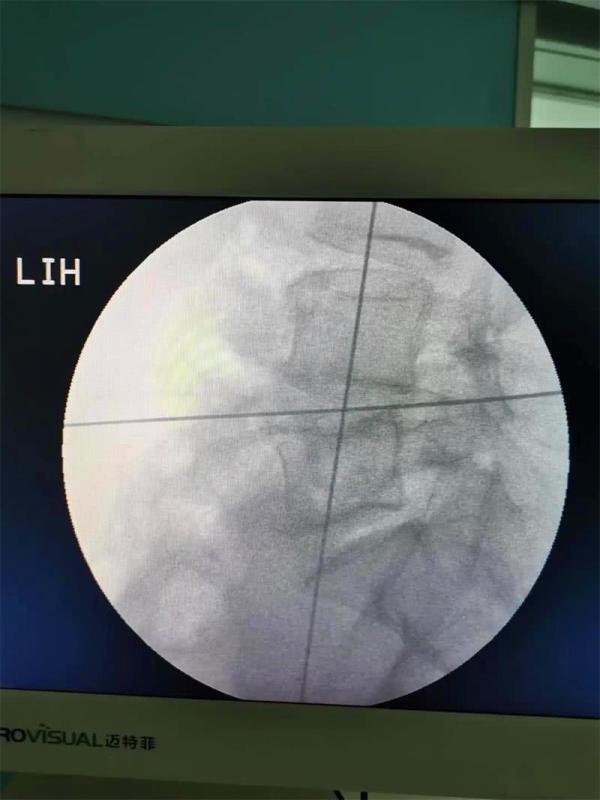

通过不到5cm的小切口,切除了椎间盘并植入大尺寸融合器,手术出血不到10毫升。术后当天,患者就感觉腰腿痛明显缓解,术后第2天已经能下床行走。该项技术的成功实施,标志着昆明市中医医院骨伤科脊柱微创水平再上新台阶。

OLIF于2012年由法国Silvestre等首先报道,是一种新的微创技术,该手术经左下腹腹外斜肌、腹内斜肌、腹横肌的肌间隙进入腹膜外间隙,在左侧腰大肌和腹主动脉之间安放工作通道,通过大血管间隙及腰大肌间入路进行手术,可明显减少手术创伤、缩短手术时间、减少术中出血、缩短住院时间及患者康复时间。

2.操作时避让开了重要血管,也不需要咬除骨头,术中出血不到10毫升,切口也仅有4—5厘米左右;